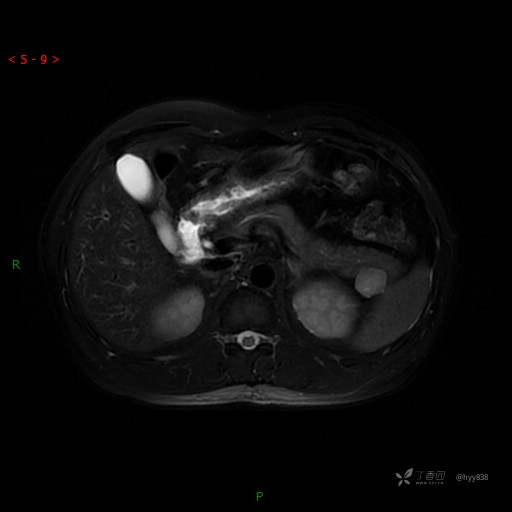

MRI(T1WI+T2WI-fs+DWI+ADC)